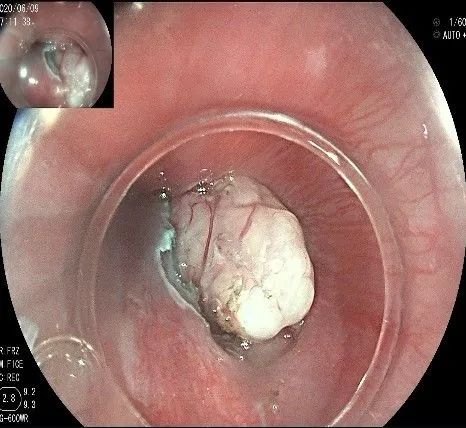

向下一直切开至齿状线处,白色为鳞状上皮,红色为腺上皮,颗粒样的部分,就是炎性息肉。切开后可见瘤体为白色,表面有血管网,质地较韧。

沿切开的边缘,从口侧开始向下进行粘膜下剥离,剥离的间隙是瘤体之上粘膜之下,期间反复进行粘膜下注射。

随着剥离的进行,瘤体与周围组织的关系越来越清晰。